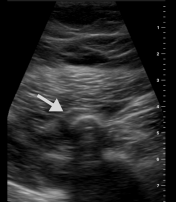

When a bullet pierces our skin, the layers of tissue slow it down. Sometimes it is moving fast enough and with enough energy that it will go straight through, but many times the bullet, or a piece of the bullet, will stop. This can happen right under the skin, in the fat layer, in the muscle, in the bone, and in our internal organs. We give each one of those levels a number.

When bullets are level 3, 4 and 5, they are more difficult to remove. You may be advised that the risk of taking the bullet out is worse than what will happen if the bullet stays inside you.

Knowing what level your bullet is can help you plan how to manage it.